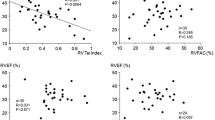

Discrimination of the SVC and IVC areas for normal versus high mRAP

Using an mRAP cut-off point of 5 mmHg, the SVC area in the standing position showed the strongest discrimination, followed by the SVC area in the supine position and the IVC area in both positions (AUC, 0.90; 95% confidence interval [CI], 0.76–1.00 for the SVC area in the standing position; AUC, 0.81; 95% CI, 0.63–0.99 for the SVC area in the supine position; AUC, 0.78; 95% CI, 0.55–1.00 for the IVC area in the standing position; and AUC, 0.74; 95% CI, 0.50–0.99 for the IVC area in the supine position), regardless of adjustment for BSA (AUC, 0.91; 95% CI, 0.77–1.00 for the SVC area in the standing position; AUC, 0.78; 95% CI, 0.59–0.98 for the SVC area in the supine position; AUC, 0.77; 95% CI, 0.55–0.98 for the IVC area in the standing position; and AUC, 0.72; 95% CI, 0.49–0.94 for the IVC area in the supine position; Fig. 4). Nevertheless, no statistical difference was observed between each situation.

Receiver operating characteristic (ROC) curves. ROC curves with the superior vena cava (SVC) and inferior vena cava (IVC) areas adjusted by body surface area in both standing and supine positions for identifying mean right atrial pressure > 5 mmHg. Abbreviations: AUC, area under the receiver operating characteristic curve; CI, confidence interval